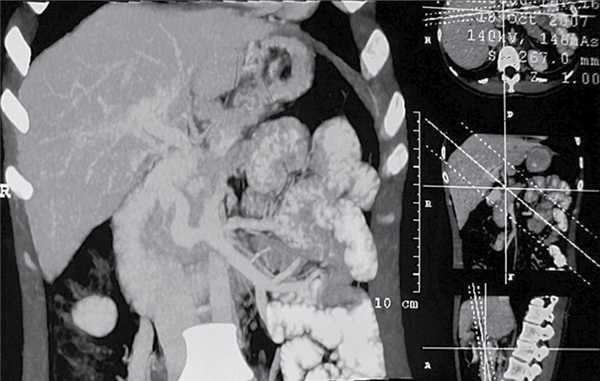

Компьютерная томография органов брюшной полости от 15.09.13: по сравнению с исследованием от 2007 г. отмечается некоторое уменьшение размеров печени в фронтальном направлении с сохранением вертикального размера. Отмечается повышение степени неоднородности печеночной паренхимы. В VIII сегменте печени визуализируется образование округлой формы 24×20 мм равномерное в артериальную фазу и гиподенсивное в венозную фазу. В других отделах печени также определяются аналогичные образования меньшего размера (вероятнее всего, очаги регенерации). Свободная жидкость не обнаружена, вокруг головки поджелудочной железы сохраняются прежнего калибра извитые венозные сосуды, анастомозирующие с ветвями брыжеечной вены, расширена яичниковая вена. Заключение: картина нарастания структурных изменений паренхимы печени, признаки портальной гипертензии (рис. 5).

Рис. 5. Спиральная компьютерная томограмма пациентки Л. через 7 лет после СРВШ. а — КТ-признаки повышения степени неоднородности контрастирования печеночной паренхимы, визуализация в VIII сегменте участка сниженной плотности (очаг регенерации); б — КТ-признаки множественных сосудистых анастомозов вокруг головки поджелудочной железы с ветвями брыжеечной вены и левой почечной веной, расширение яичниковой вены.